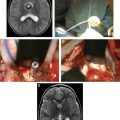

VMs of the abdomen can be focal, multifocal (for example, blue rubber bleb nevus syndrome [BRBNS]), or diffuse. These lesions may result in gastrointestinal or intraperitoneal hemorrhage. Symptomatic focal lesions can be treated with endoscopic sclerotherapy or segmental bowel resection. Patients with multifocal VMs who require chronic blood transfusions may undergo surgical eradication of all the luminal lesions with intraoperative endoscopic assistance. Nonsurgical management (pharmacologic therapy or endoscopic treatment) for BRBNS has not been durably effective; however, early experience shows some optimism for sirolimus in this regard. In contrast, diffuse VMs are treated with selective excision of the symptomatic area. These lesions typically encompass the left colon to the anus and are managed with left colectomy, mucosal proctectomy, and coloanal pull-through. In some patients repeated sclerotherapy of the submucosal anorectal VM may avoid or delay the need for pull-through.